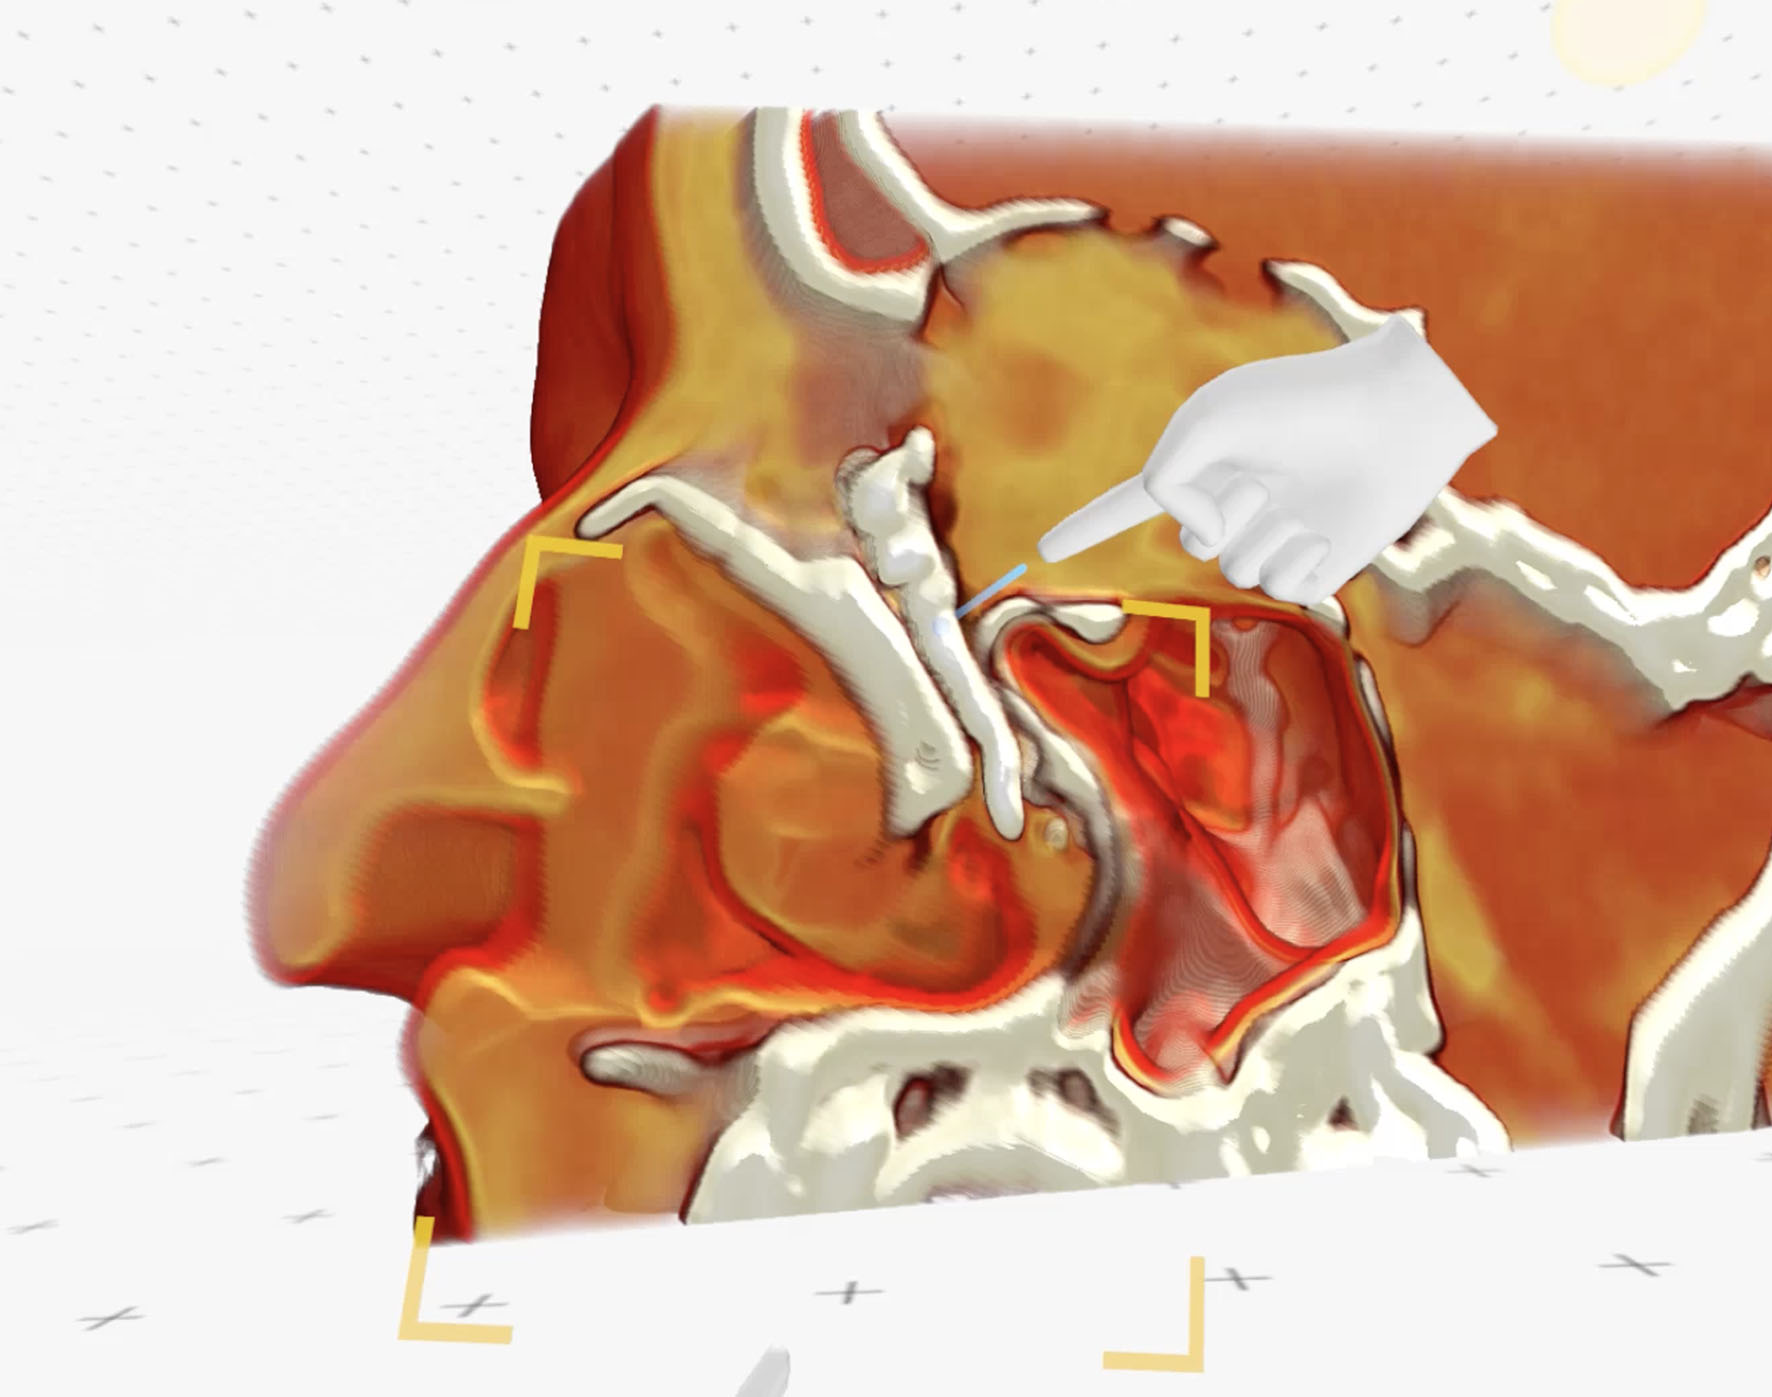

Nasal endoscopy examination was normal other than a deviated septum. Further 3D-dimensional reconstructions were performed from the CT-DCG data using the Meshlab (Visual Computing Lab, CNR-ISTI, Pisa, Italy) and Blender software tools (Blender Foundation, Amsterdam, Netherlands).

The reconstructions showed the intricate relationship of the lesion with the compressed lacrimal system (Fig. 5). The surgical plan was a careful excision.

Although the shape of the lacrimal sac was a little irregular on the CT-DCG, the sac integrity was good. Three-dimensional reconstructions from the postoperative CT-DCG showed good anatomical integrity of the lacrimal drainage system (Fig. 11).

Figure 11. Postoperative three-dimensional reconstruction of the lacrimal system (right – well filled lacrimal system with smooth walls; left – well filled lacrimal system with irregularities within inferior part of the lacrimal sac